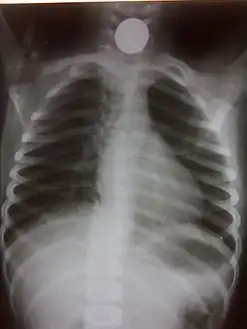

A coin seen on AP CXR in the esophagus

A coin seen on lateral CXR in the esophagus